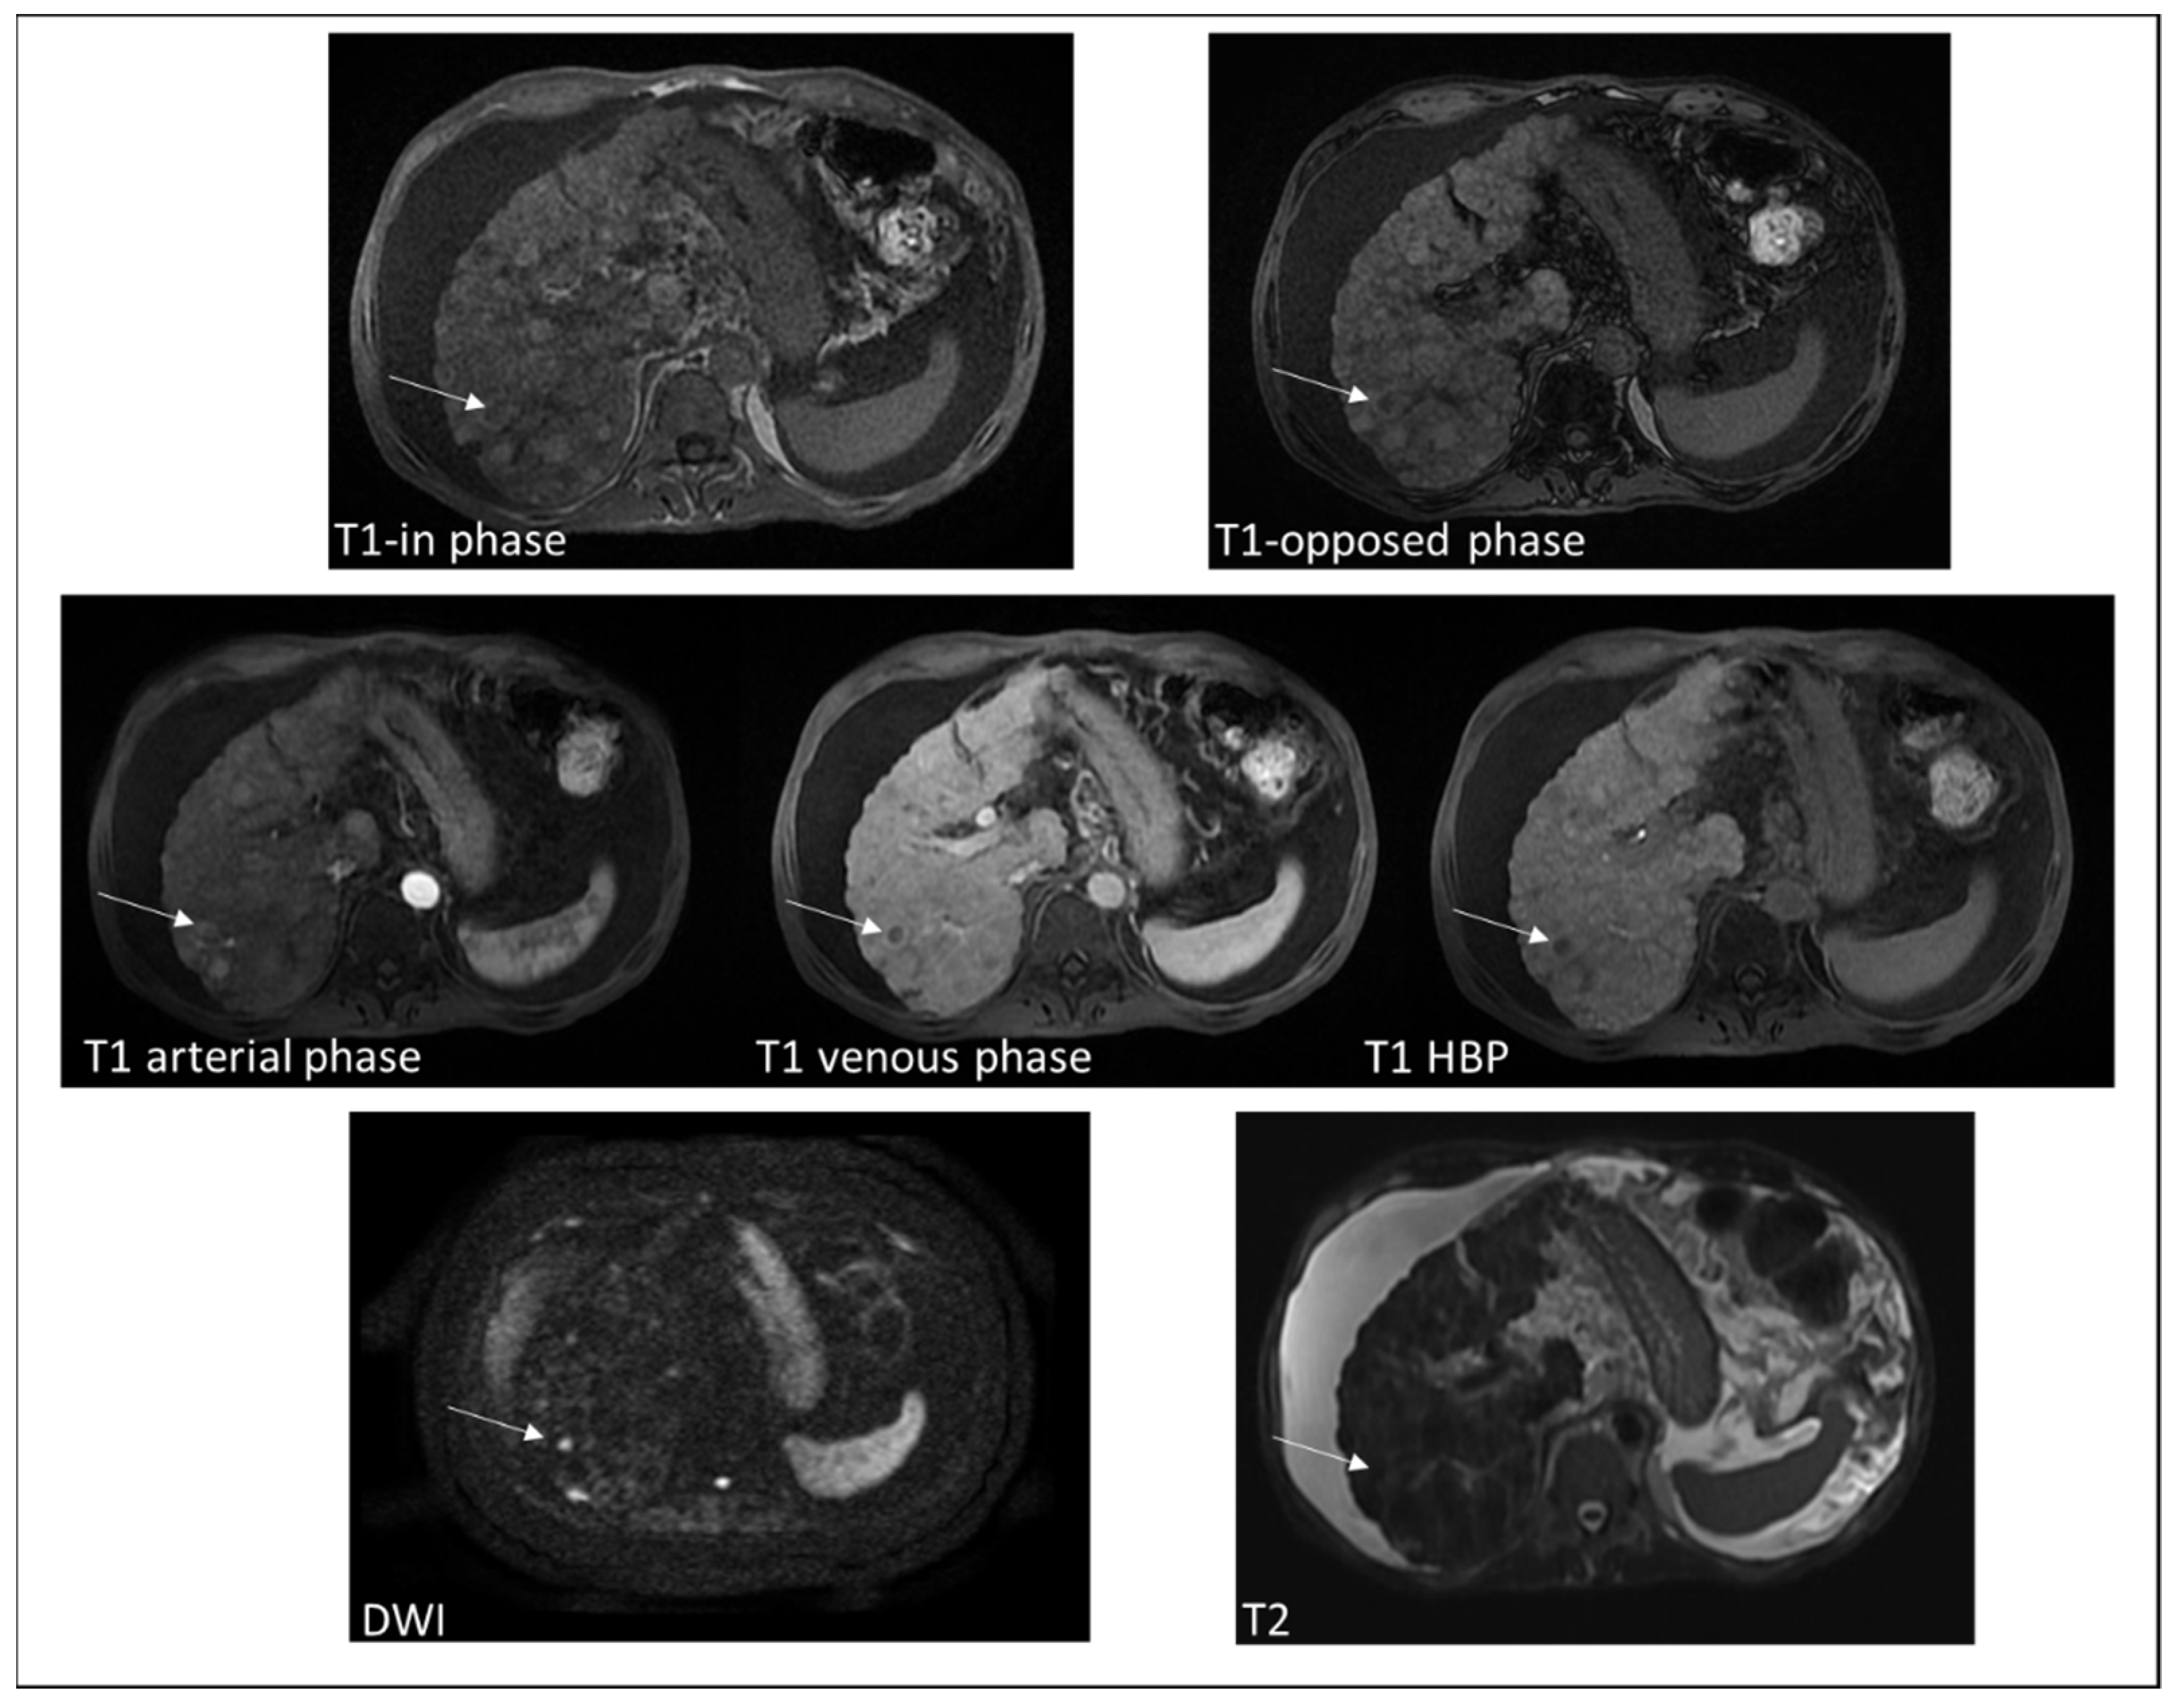

4.1. Hepatocellular Carcinoma

4.2. Extramedullary Hematopoiesis